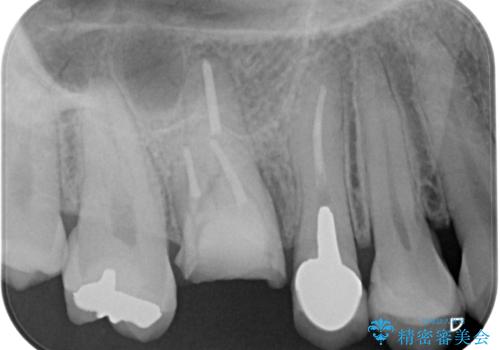

割れてしまった奥歯 1DAYインプラント治療

- 近医にて治療がなかなか進まないとのことで来院された患者様です。

詰めている材料を外したところ、目視で確認できるほど割れており、要抜歯との説明をし、インプラント治療を行うこととしました。

骨量が十分にあることが3次元CTより確認されたため、事前に仮歯を用意した上で、抜歯即時埋入インプラントによる補綴治療を行うこととしました。